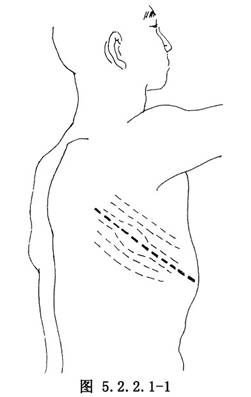

(1)切口:根據腫瘤的範圍,在腫瘤未侵及淺層肌肉和皮膚時,可沿瘤體的長徑作切口(圖5.2.2.1-1)。若腫瘤已累及皮膚,應沿瘤體的長徑作梭形切口,切緣距腫瘤3cm以外,連同受累的皮膚、肌層與腫瘤一併切除(圖5.2.2.1-2)。